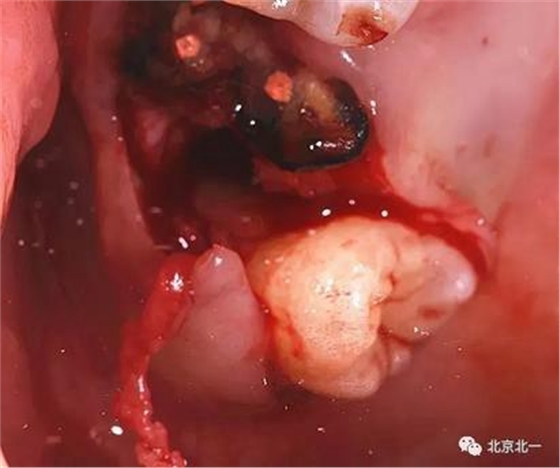

圖六:牙冠完整被挺松。